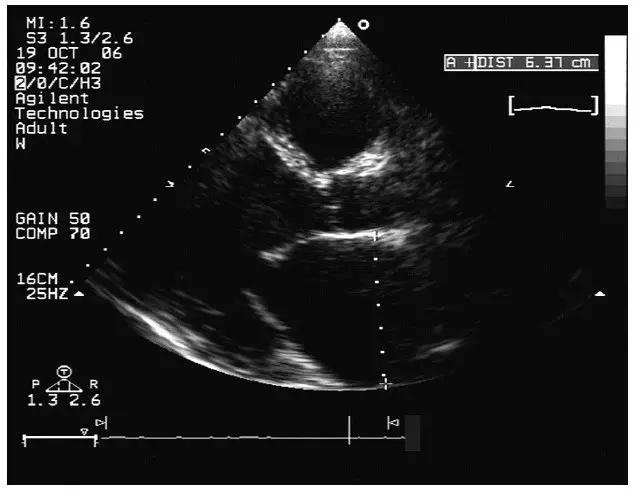

1.心腔明显扩大,以左心房和左心室扩大为主(图11-1-1)。室间隔弓形前移,左心室后壁弓形后移,左心室呈球形扩大,左心室流出道明显增宽,内径常大于35 ~ 40mm;右心室扩大相对较轻。

图11-1-1 扩张型心肌病心腔扩大

心腔明显扩大,以左心房和左心室扩大为主